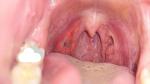

Здравствуйте, горло не болит, температуры нет, уши не закладывает. Есть "гыки", чаще на нервной почве получаются. Иногда хочется прочистить горло. Было чувство кома в горле, пропало. Больше с правой стороны. Брызгала горло ларингосептом, часто болела ангиной раньше. Посмотрела на горло, начала нервничать, была кровь в слюне, выяснила что кровоточит зуб. Сегодня вышел сгусток крови в слюне, боюсь, что может из горла или больше паники. Проверяю горло каждый день по 7 раз, фото, видео, стресс. Ста